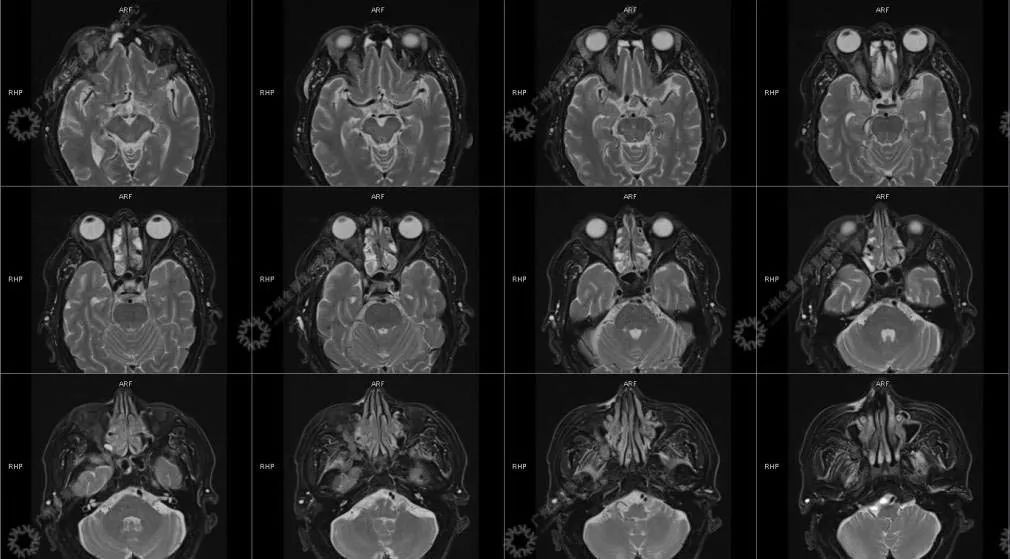

患者:男性, 71 岁

主诉:视力下降 2 年

现病史:双眼部隐痛、流泪,视力下降 2 年

结合影像及实验室检查,临床最终考虑 IgG4 相关性疾病。